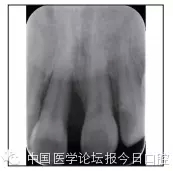

全口曲面體層片(圖3)顯示,患者全牙列牙槽骨吸收;根尖片(圖4)示11近中牙槽骨角形吸收已達根尖1/3,21牙槽骨嵴頂吸收至根1/2,23牙槽骨近中骨板角形吸收至根1/2。磨牙區(qū)骨嵴頂吸收3mm。治療前頭顱側位片見圖3,治療前ODS模型見圖5。

圖4 治療前根尖片